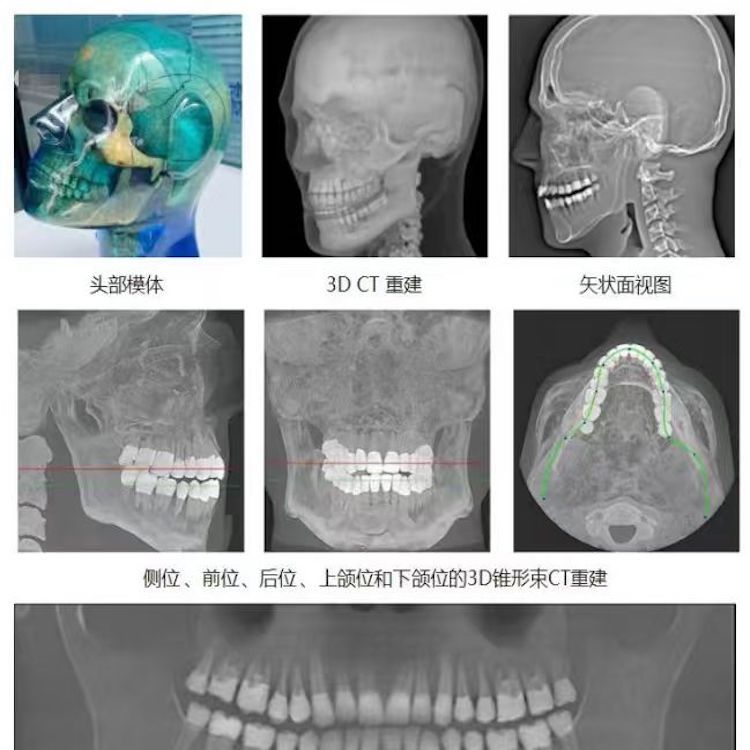

頭部模體是頭部診斷放射學的參考標準,該模體旨在協助技術和臨床人員,在大多數需要精細解剖細節的放射學程序中選擇、監測、培訓和驗證掃描參數。 模體為研究人員、臨床醫生和技術人員提供了一致性的工具。它非常適合確定最佳系統設置、調試新設備、監測系統性能和培訓牙科X射線、全景X射線、CT和錐束CT程序。 這個模體包括一個可調節的支架,用于在錐束 CT 或全景X射線系統中定位。模體的下頜略微張開,前牙垂直排列,以復制正確的咬合引導定位 。 請注意,實際咬合引導無法在這個產品中定位。 頭部模體是由專有組織等效材料制成的。由組織模擬樹脂制成,這些樹脂模擬X射線對人體的衰減特性,適用于CT和治療能量范圍(50keV-25MeV)。 模體在大小和結構上都近似于平均男性頭部 。該模體包括詳細的3D擬人化解剖結構, 包括大腦、骨骼、喉、氣管、鼻竇、鼻腔和牙齒。骨骼包括皮質和骨小梁的分離。牙齒包括明顯的牙本質、牙釉質和包括神經的牙根結構。鼻竇完全張開。

頭部模體特點 1. 詳細的解剖特征; 2. 確定法蘭克福平面以確保正確對齊; 3. 50 keV 至 25 Mev 的組織等效值; 4. 具有六個自由度的定位支架; 5. 包括泡沫內襯手提箱; 6. 12個月保修。

功能和應用 1. X射線 ,全景X射線 ,CT和錐束CT系統; 2. 學習如何正確定位頭部以獲得最佳圖像; 3. 測試重建技術和算法 ,用于植入物規劃和頜面部重建; 4. 在實施新設備和新技術期間培訓并評估人員; 5. 驗證圖像質量的一致性。